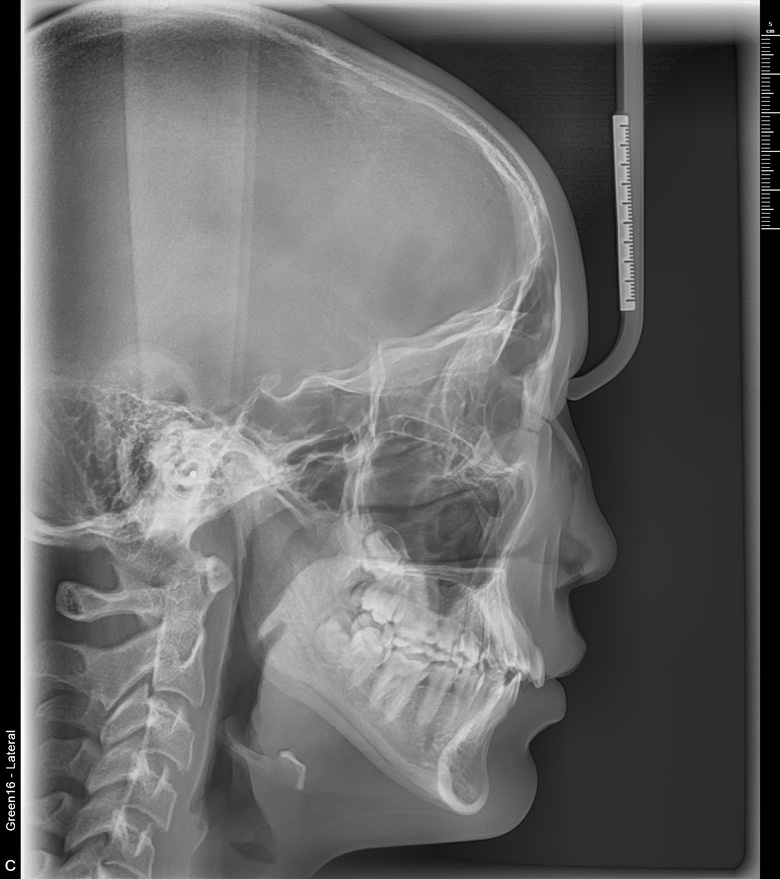

치료 전 사진입니다.